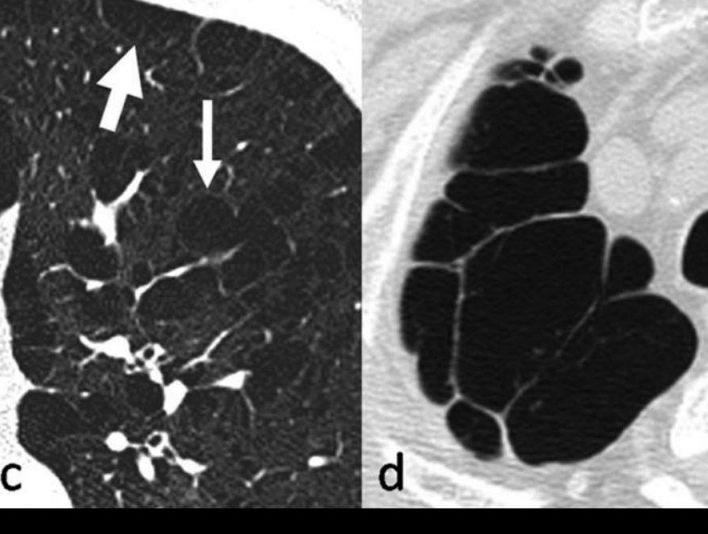

Patron intesticial grueso

Imágen en riel o tranvía: inflamación de pared bronquial

Manguitos peribronquiales: engrosamiento visto de frente

Bronquitis crónica

Manguitos peribronquiales: bronquitis crónica

Manguitos peribronquiales

Tranvía